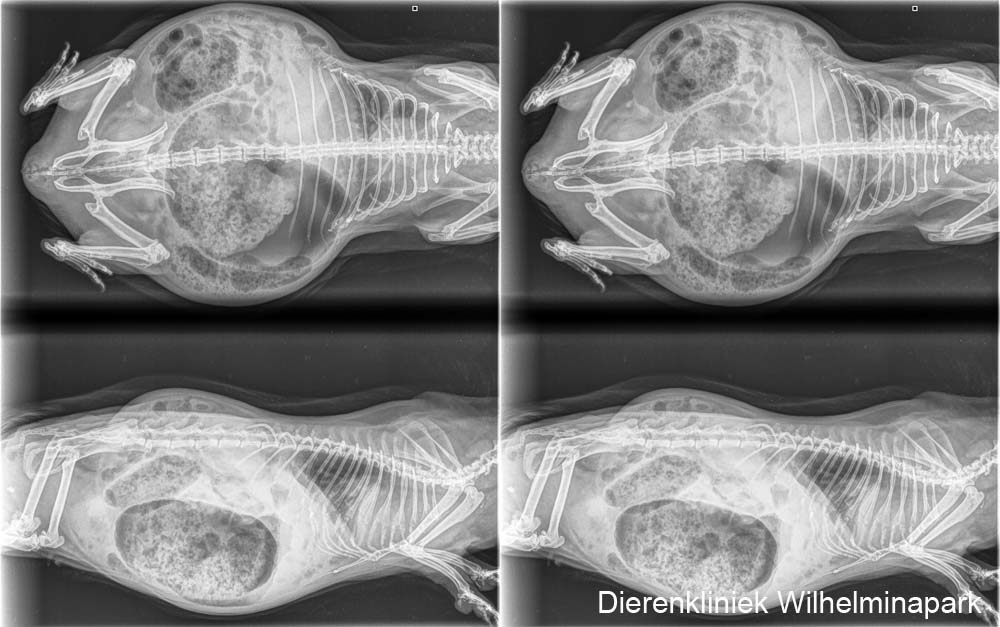

We hebben rontgenfoto's van vier zijden gemaakt. Van links boven naar linksonder met de klok mee: op de rug liggend (VD) en borst buikligging (DV) en twee keer in zijligging - op rechterzijde liggend (SD) en op de linkerzijde liggend (DS) - om een zo goed mogelijk overzicht van de longen en het hart te krijgen.

We hebben de röntgenfoto's laten beoordelen. Zie hieronder: er is een verdenking van een pneumonie (een longontsteking).

Uit het onderzoek kwam een infectie met mycoplasma naar voren.

Beide cavia's zijn goed genezen met de oogzalf en antibioticum, na 2 weken waren de klachten volledig over.